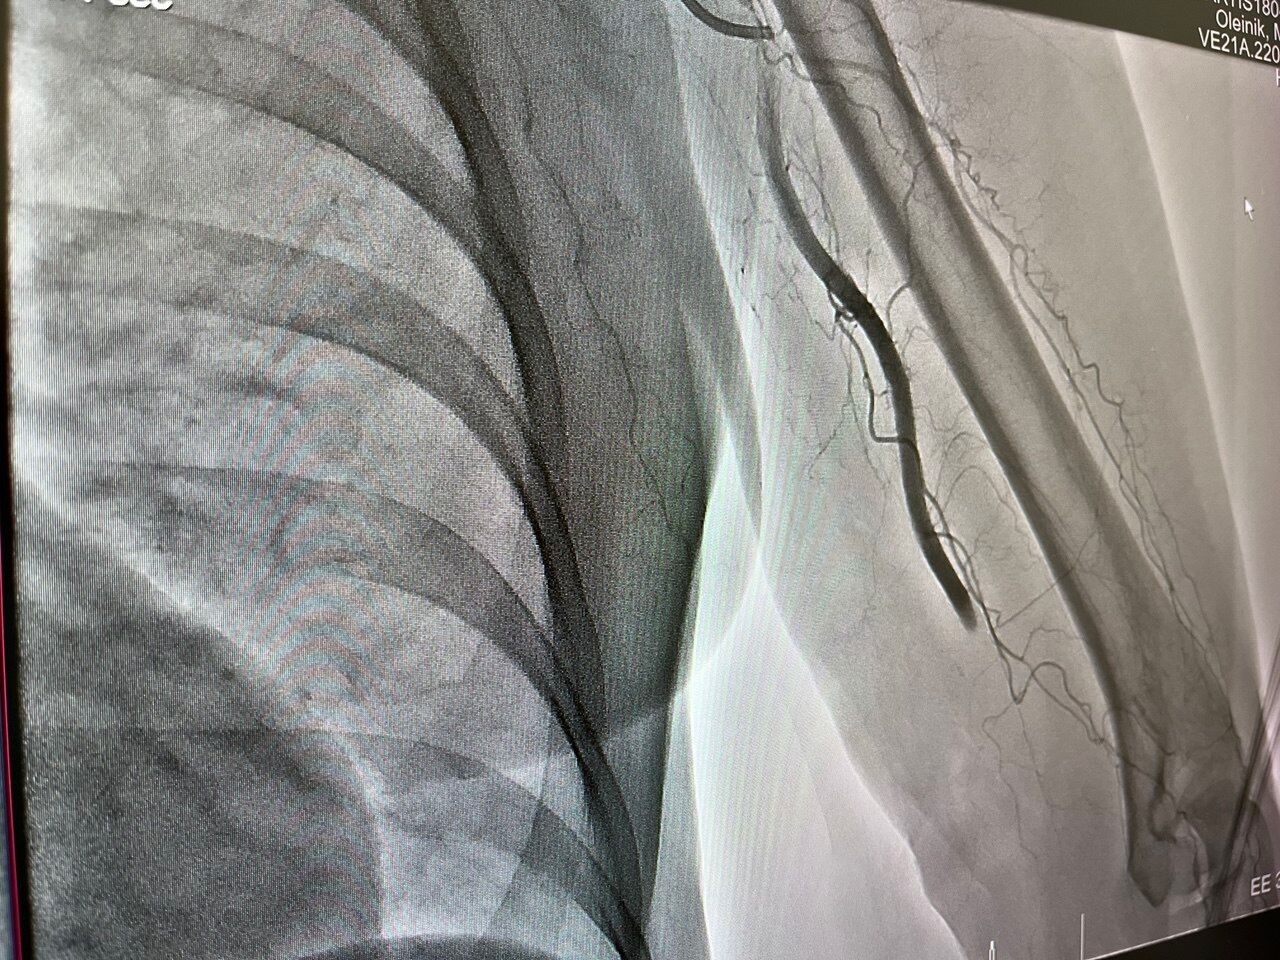

Была проведена процедура тромбэкстракции. Сообщается, что через бедренную артерию микрокатетером специалисты достигли места закупорки сосуда и устранили тромб.

В результате практически сразу кровоснабжение пришло в норму. Сейчас жизнь и здоровье пациентки находятся вне опасности.